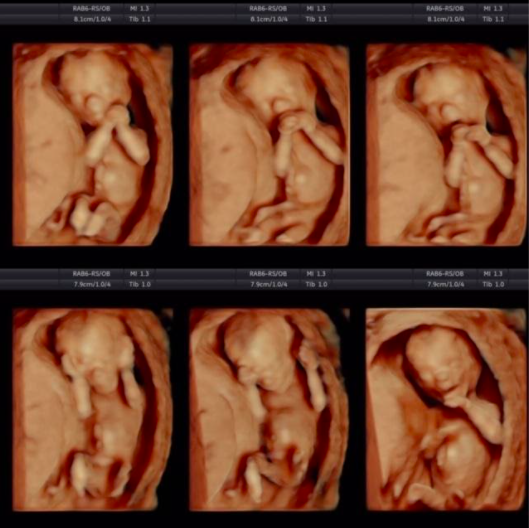

Ngoài ra, chiều dài xương đùi của thai nhi cũng là yếu tố có thể giúp xác định giới tính. Thai nhi có hình dáng tròn thường liên quan đến các bé gái, trong khi thai nhi hình dáng dài lại thường là dấu hiệu của bé trai. Những thông tin này thường được các mẹ bầu truyền tai nhau từ nhiều thế hệ, tạo nên những câu chuyện thú vị quanh việc dự đoán giới tính.

Hình ảnh siêu âm thai luôn mang lại niềm vui và sự hồi hộp cho các bậc phụ huynh. Khi xem các bức ảnh siêu âm, các bậc cha mẹ có thể thấy những thay đổi nhỏ nhưng đáng yêu của thai nhi qua từng tuần. Chẳng hạn, ở tuần thứ 6, hình ảnh túi thai như một chiếc nòng nọc, và đến tuần thứ 7, các đặc điểm như ngón tay, ngón chân bắt đầu hình thành rõ nét hơn.